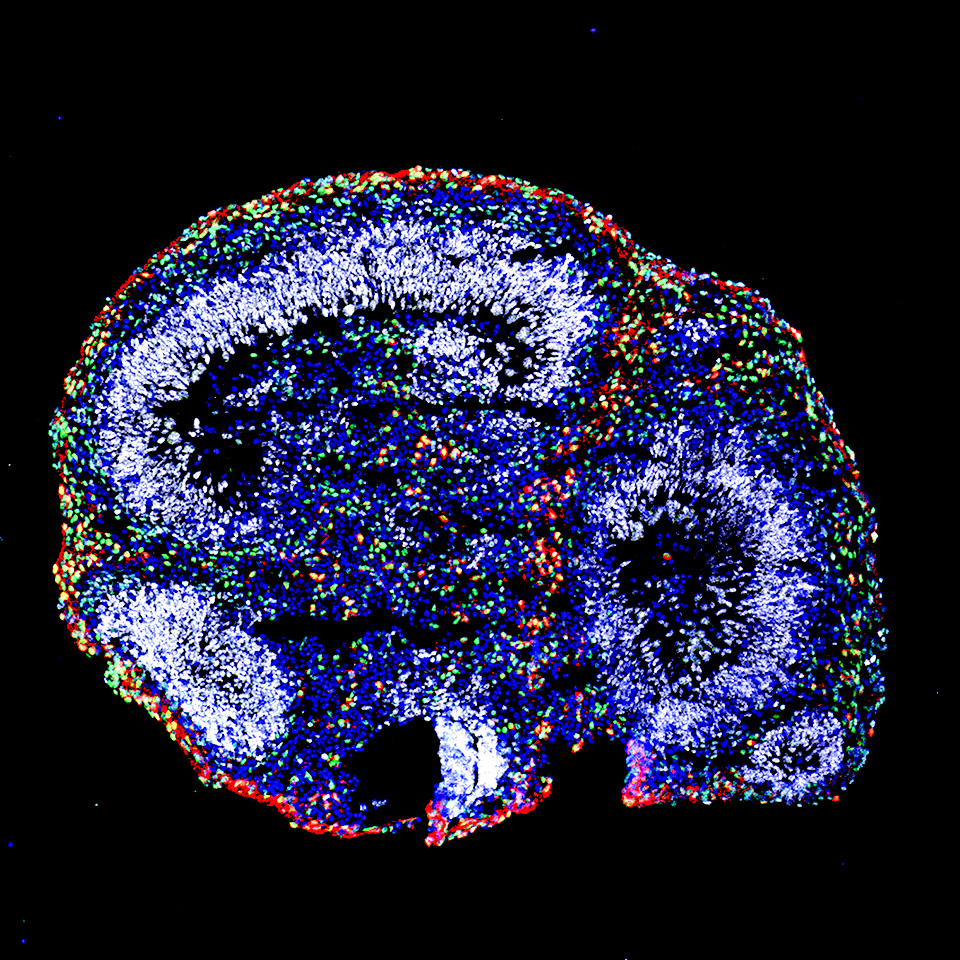

研究対象とする最先端技術の一つがオルガノイド技術。培養皿でiPS細胞など多能性幹細胞から作られる3次元の組織はオルガノイドと呼ばれ、神経領域では大脳、小脳、海馬、中脳、視床、脊髄など、その他の臓器では腎臓、肝臓、胃、腸などの作製に成功している。

生体内と同じ構造を持つ組織を体外で再現できるため、疾患が発症する仕組みの解明や創薬への応用が期待される。「技術そのものはもちろん、その倫理的検討も前例がなくフロンティア。自分たちで未来を描いて議論するしかありません」。

ヒトの脳のように意識を持つ可能性があると言われる大脳オルガノイド。しかし実際は、脳の局所的な構造を豆粒ほどの大きさで再現できているのが現状だ。澤井助教は、大脳オルガノイドが意識を持つと推定するのはやや尚早とした上で、意識を持つことをただ問題視するのではなく、どのような意識を持つかを議論することが重要だと考える。「最先端であるほど得られる情報は少ない。技術そのものを正しく把握することすら難しく、議論が飛躍しがちです。でもASHBiやCiRAでは、最前線でその技術を開発・応用している科学者たちと直接意見を交わすことができます。正確な情報に基づいて議論しなければ、過度に規制してしまうだけでなく、規制すべきところを見逃す可能性もある。偏った情報に囚われてフィルターのかかった議論をしないよう心がけています」。

左と中央は培養37日の大脳オルガノイド。右は培養52日。生体で作られる脳の層構造が脳オルガノイドでも同様に再現され、培養37日に比べて培養52日のオルガノイドでは、より成熟した層構造を形成している(写真提供・坂口秀哉氏〈理化学研究所〉)